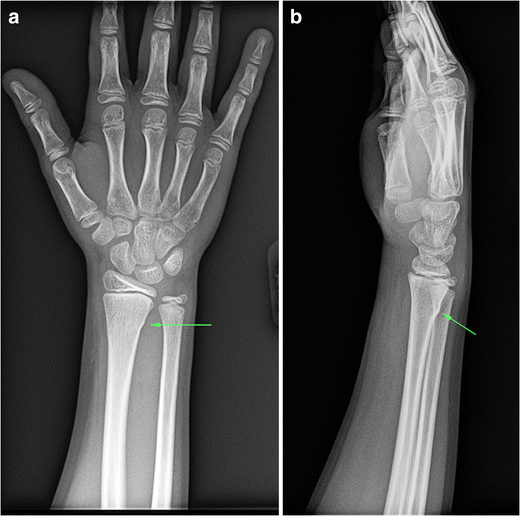

Fall on outstretched hand (foosh) is most common in older population. Buckle fractures of the distal radius are common in children between 2 and 12 years of age buckle (torus) fractures occur when the bony cortex is compressed and bulges, without extension of the fracture into the cortex ( figure 1 ). Abzug jm, little k, kozin sh.

Distal radius fractures are the most common site of pediatric forearm fractures and generally occur as a result of a fall on an outstretched hand with the wrist extended. Distal radius fractures are a predictor of subsequent fractures. The most common wrist fracture is a distal radius fracture, when the radius (the larger bone in the forearm) is fractured on the distal end, near the wrist.

Fracture remodelling distal radius fractures in children account for up to 45% of all paediatric fractures. This often occurs when a child falls on an outstretched hand that is extended backward. A buckle fracture can often happen in children because their bones are softer than the bones of an older adolescent or adult.